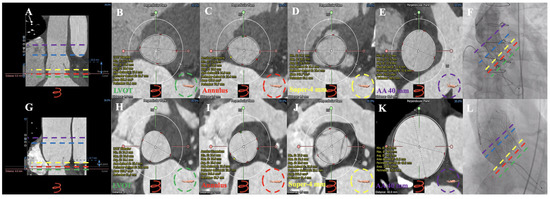

3.2. MDCT Evaluation and Anatomical Classification

3.3. Operation